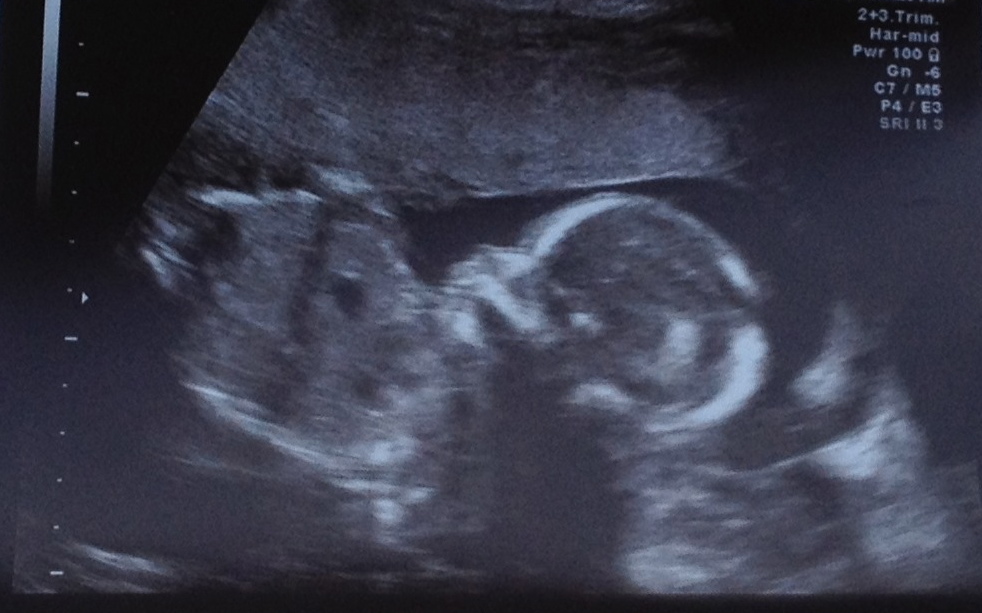

20 Week Scan Picture

We had our 20 week scan today and it was lovely to see bubs and everything is good which is great news :)

I personally can't see anything in the scan pics that might give me any clues but thought I would check with you guys too......

Anyone have any thoughts on the skull/gender etc??

No gender clues in the lower region...and that's a tricky skull. In one shot it looks boy, another girl. Looks like this bub wants to be team green too :))))))

Gorgeous!!! Got a potty shot?

No didnt get a potty shot, these are the only pics we have.